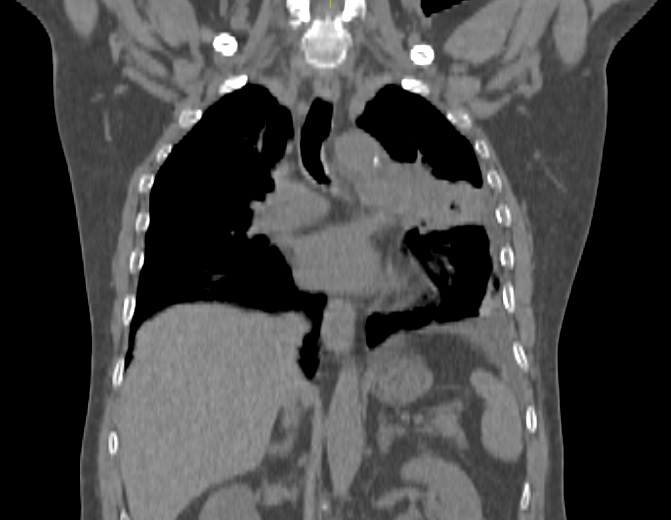

Pacientul M.L. in varsta de 56 ani, fumator de 40 ani, 20PA, s-a prezentat in clinica noastra pe data de 30.11.2022, cu diagnosticul de adenocarcinom pulmonar (neoplasm pulmonar) la nivelul lobului pulmonar superior stang, o tumora in stadiul IIIC, de dimensiuni mari T3, cu invazie ganglionara si mediastinala. Cazul a fost prezentat in Comisia Oncologica Multidisciplinara a clinicii noastre, unde s-a decis initierea tratamentului oncologic. Tumora fiind avansata loco-regional, era exclusa interventia chirurgicala in acest stadiu de boala (cancer pulmonar inoperabil).

Astfel, in perioada 5.12.2022 – 26.01.2023, pacientul a efectuat radioterapie externa cu fotoni, tehnica VMAT-CBCT, pana la doza totala DT = 66 GY/volum tinta formatiune tumorala pulmonara, un numar total de 33 fractii, concomitent cu administrarea saptamanala de polichimioterapie de radiosensibilizare, cu toleranta foarte buna.

Prezentam acest caz la scurt timp dupa finalizarea tratamentului (tratament cancer pulmonar), deoarece acesta este un caz fericit, la care s-a observat un raspuns aproape total chiar din timpul tratamentului RT, imaginile CBCT efectuate la inceputul, in timpul si la finalul tratamentului RT, pe care le atasam, aratand clar un raspuns extraordinar de bun la tratamentul efectuat.